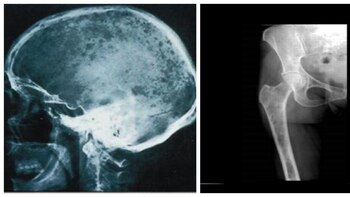

Qué es el mieloma múltiple y por qué enfermos en México quieren que se clasifique como enfermedad catastrófica

Asociaciones y pacientes entregaron 250,000 firmas para exigir que se incluya al mieloma múltiple como una enfermedad catastrófica y sea cubierta por el Insabi

Qué es el mieloma múltiple